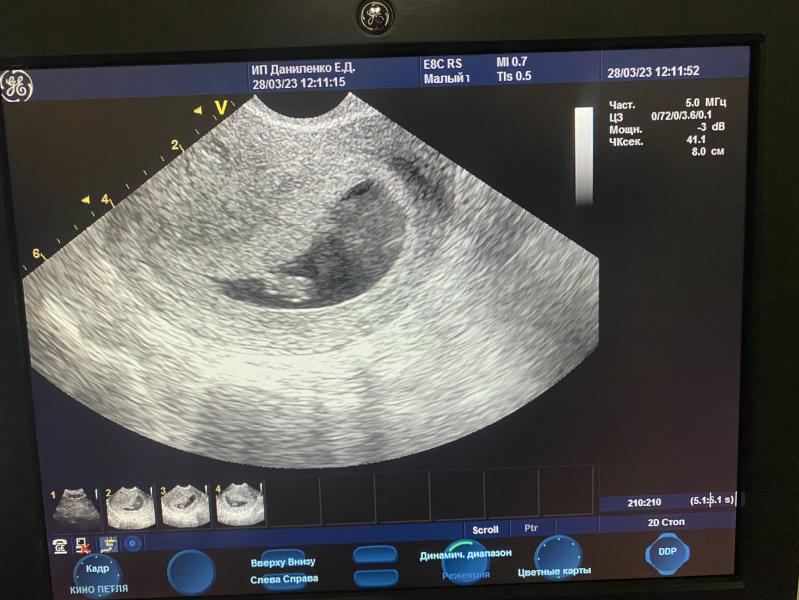

Ура! Сегодня услышала сердцебиение моего малыша! Это так трогательно и волнительно

Сегодня услышала сердцебиение 💕💕💕

28.03.2023